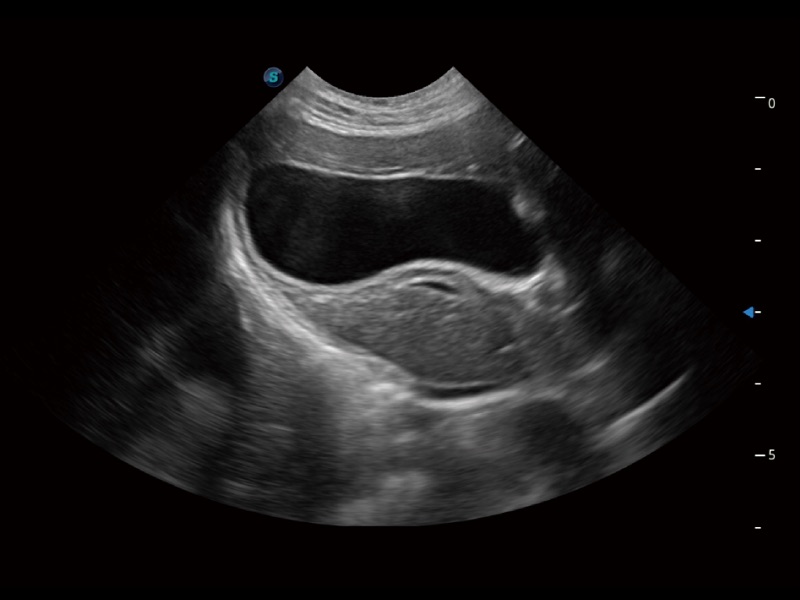

一键自动识别膀胱壁及自动测量膀胱容积,不受膀胱形状和大小的限制,帮助医生快速精准获得测量的数据。

能够基于左心室壁追踪和辛普森法,自动计算射血分数,支持多个可移动点描迹,与手动测量相比,极大节省了动物医生的时间和精力。

通过360度任意调节3条M型取样线,在同一心动周期上观察心脏不同位置的运动曲线,得到准确的心功能测量数据,有效评估心肌运动及左心室功能。